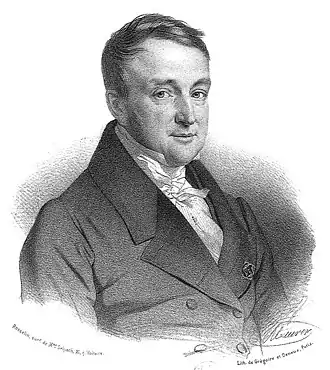

Моро де Тур, Жак Жозеф

| Жак Жозеф Моро де Тур | |

Жак Жозеф Моро де Тур (фр. Jacques-Joseph Moreau de Tours; 3 июня 1804 — 26 июня 1884) — французский психиатр, один из основателей клинической психофармакологии.